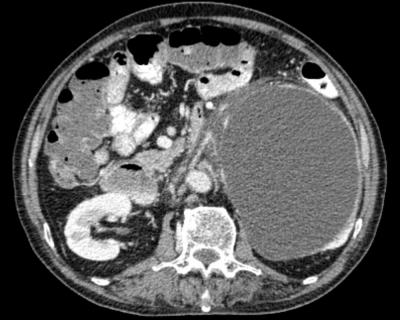

abdominal mass with haematuria

Figure 1: Contrasted computed tomography showing huge left homogenous and regular retroperitoneal lesion with peripheral enhancement on axial view